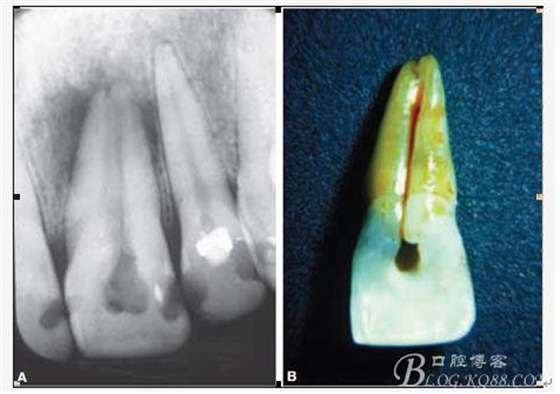

D、牙根的內(nèi)外吸收 這個目前具體機制也不是非常明確,只要能想到這個層面,通過X片檢查不難發(fā)現(xiàn),尤其到了有臨床癥狀的時候;